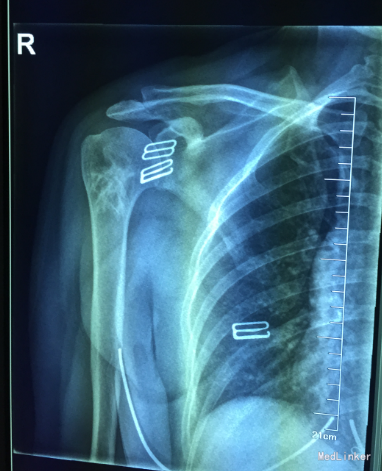

患者,中年女性,以“右肩疼痛伴活动障碍2年余”入院查体:约胸8椎体棘突及右侧胸背部压痛及叩痛阳性,不伴放射痛,颈椎及腰椎无明显压痛,脊柱活动度基本正常,肱骨近端压痛轻度阳性,右肩活动受限,外展95°,前屈95°,后伸15°。

右肩X片示:右肱骨近端髓腔片状高密度混杂影,行CT为右侧肱骨近端改变,考虑骨纤维异常增生症可能。

行臂丛麻醉下行右肱骨近端病灶刮除植骨术,将骨髓腔内病灶组织完全刮除.术后病理诊断为:骨纤维异常增生

诊断:右肱骨近端骨纤维异常增生症.讨论:术后给予消肿,止痛,胸背疼痛较前缓解,伤口愈合良好,局部无红肿硬节及渗出,出院后应将逐步适量功能锻炼;伤口定期换药,术后两周拆线,加强营养支持,补钙治疗,促进骨愈合。